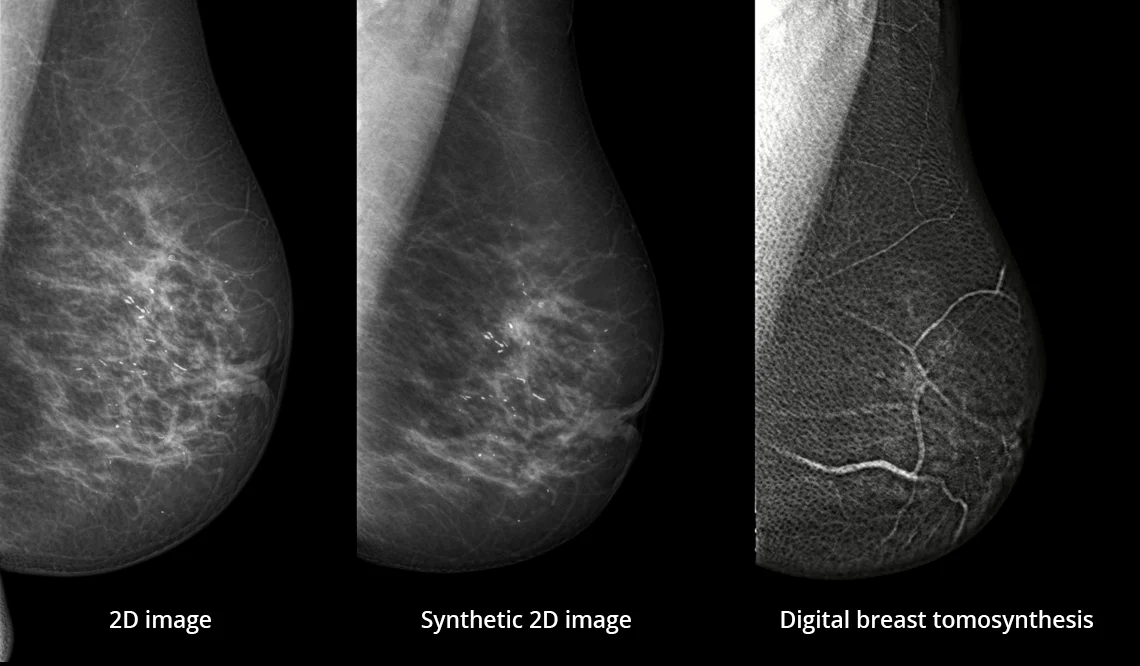

Zalety cyfrowej tomosyntezy piersi (DBT)

Cyfrowa tomosynteza piersi (DBT) tworzy warstwowy zestaw obrazów piersi, przez który można przewijać. Takie podejście eliminuje problem nakładających się struktur tkanek, co prowadzi do zwiększenia czułości i swoistości badania.

Unikalne podejście do cyfrowej tomosyntezy piersi

Unikalna metoda obrazowania Continuous Sync-and-Shoot™ firmy Planmed umożliwia uzyskanie obrazów tomosyntezy pozbawionych rozmycia ruchowego. Dzięki temu obrazy są wyjątkowo wyraźne i zapewniają doskonałą widoczność mikrozwapnień oraz innych drobnych struktur tkankowych.

Obrazy Kliniczne Planmed Clarity 3D